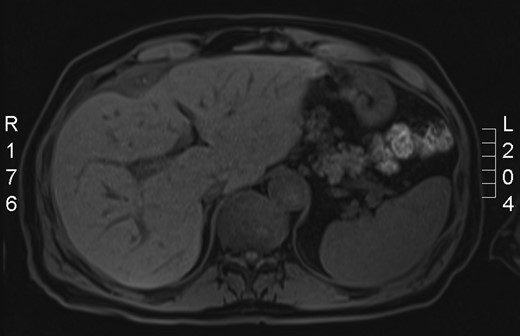

On discharge, he required regular visits to his general practitioner for antibiotics. He was seen at the clinic as a follow-up for his ongoing right upper quadrant pain. A magnetic resonance imaging (MRI) abdomen (Fig. 2) was performed, which showed small, oval-shaped, thick wall collection anterior to the capsule of the liver. After the MRI, we have decided to book him for surgery.